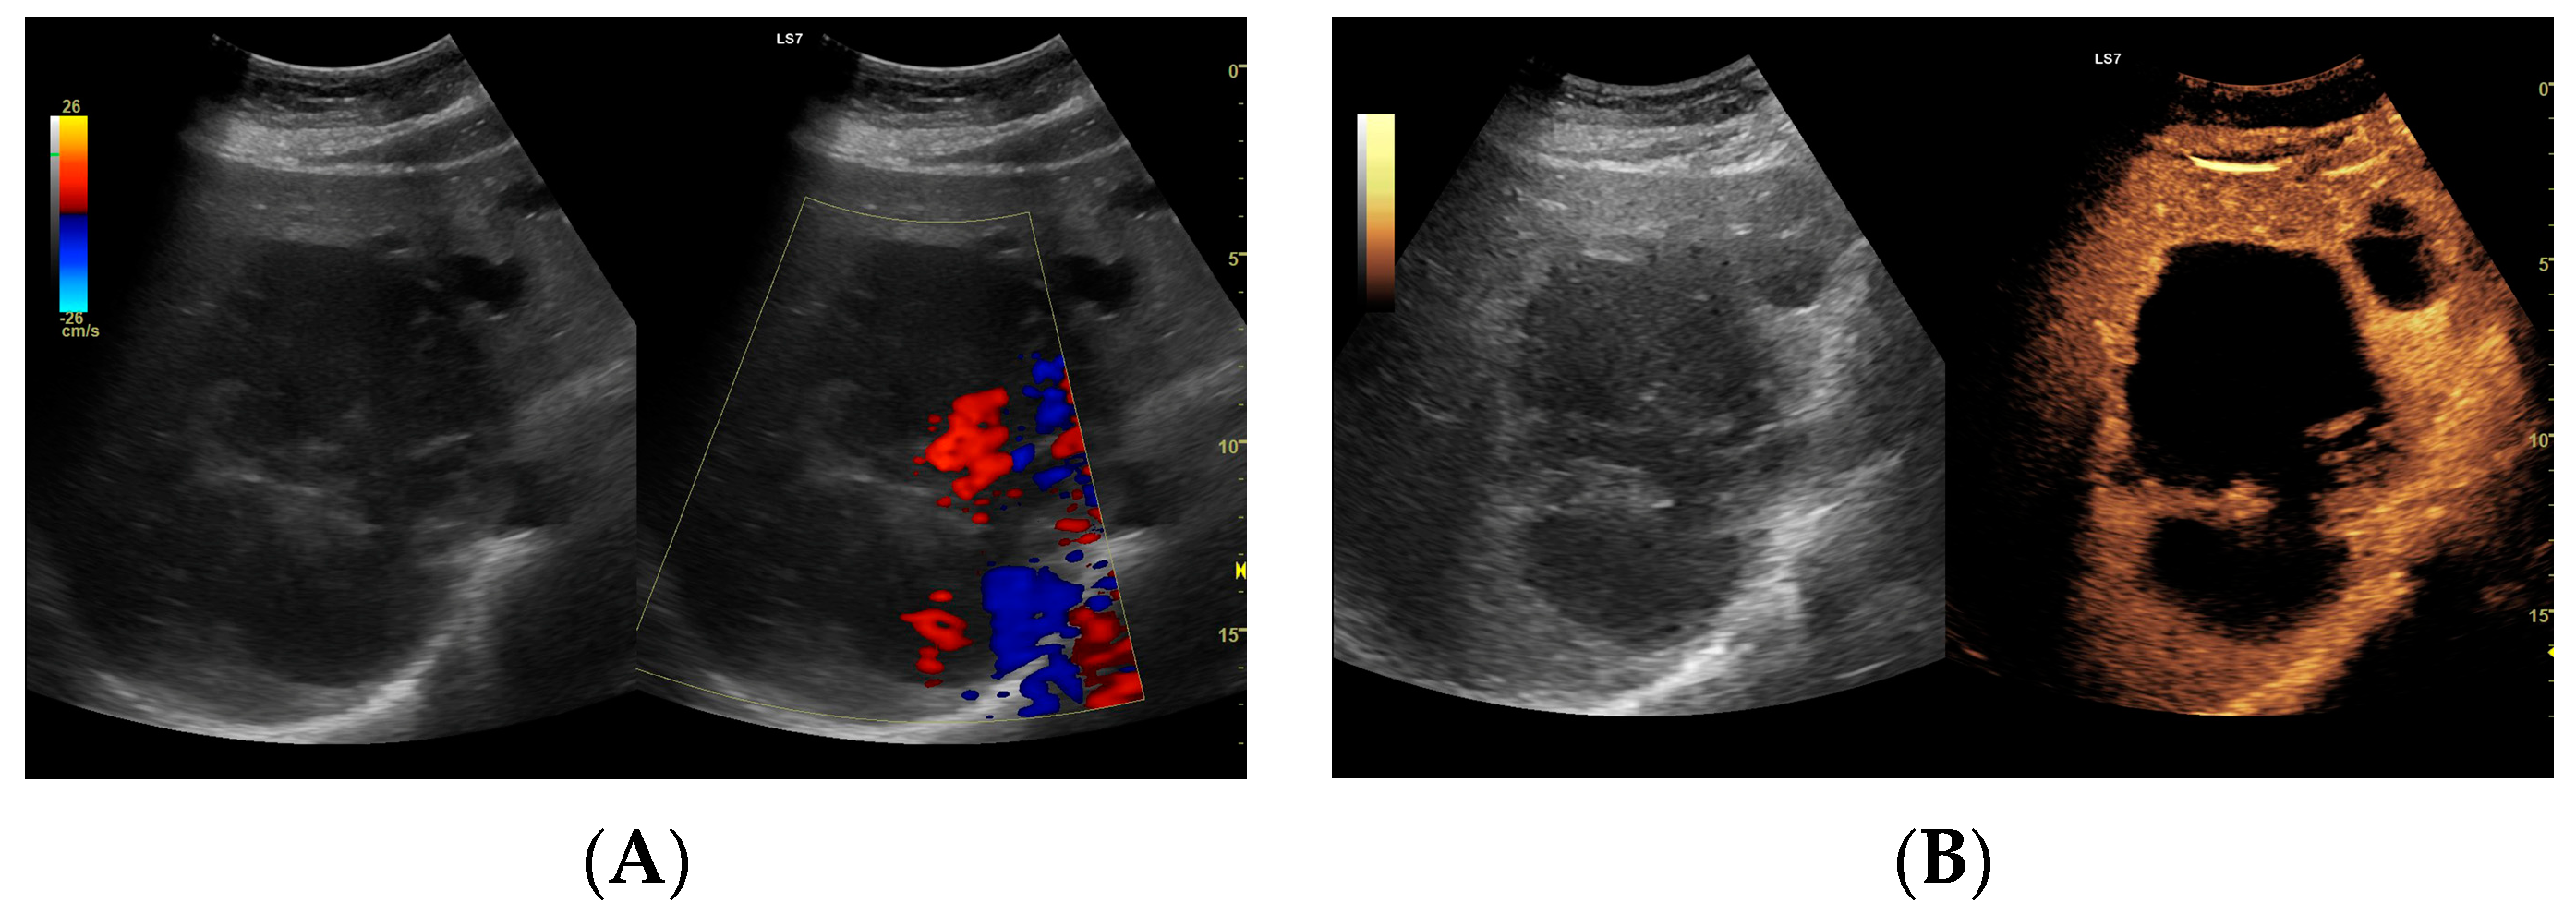

Figure 5.

(A) Ultrasound and color Doppler: The transverse view shows a focal lesion in the right liver lobe, identified as a type III–, lacunar abscess, with visible septa in B-mode. In this case, it is possible to clearly classify the lesion as a type III abscess and determine its actual fluid component. (B) CEUS arterial phase: The enhanced abscess capsule and septa are visible. The total abscess was estimated to be 124.16 cm² from CEUS, while the fluid fractions were estimated at 57.43 cm² on B-mode and 61.55 cm² on CEUS, respectively, which, according to the methodology used, translates to 914.86 mL in B-mode and 980.49 mL in CEUS, respectively. The enhancement of the abscess capsule is slightly higher than that of the parenchyma. The lesion remains in the active phase of inflammation, although with less intensity.